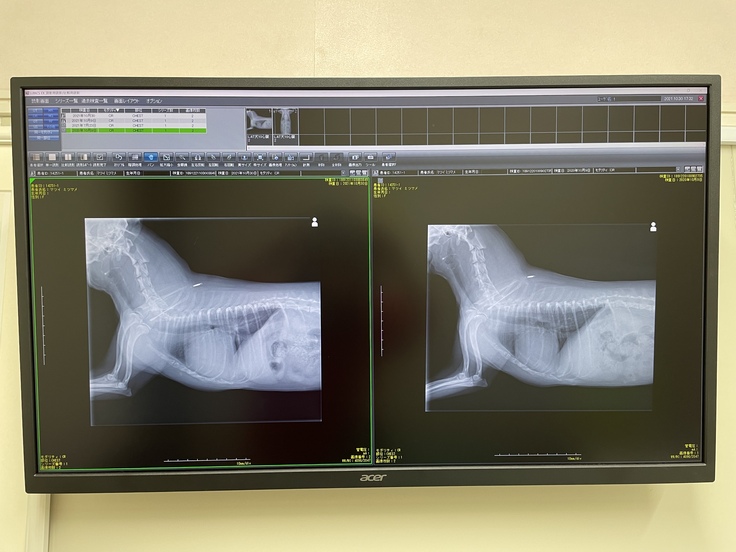

右が今年7月に、呼吸困難を起こした時の画像です。肺に水が既に浸潤して、心臓の輪郭がボヤけています。

右が昨年10月の画像、今年10月撮影。心肥大により気管が圧迫されています。